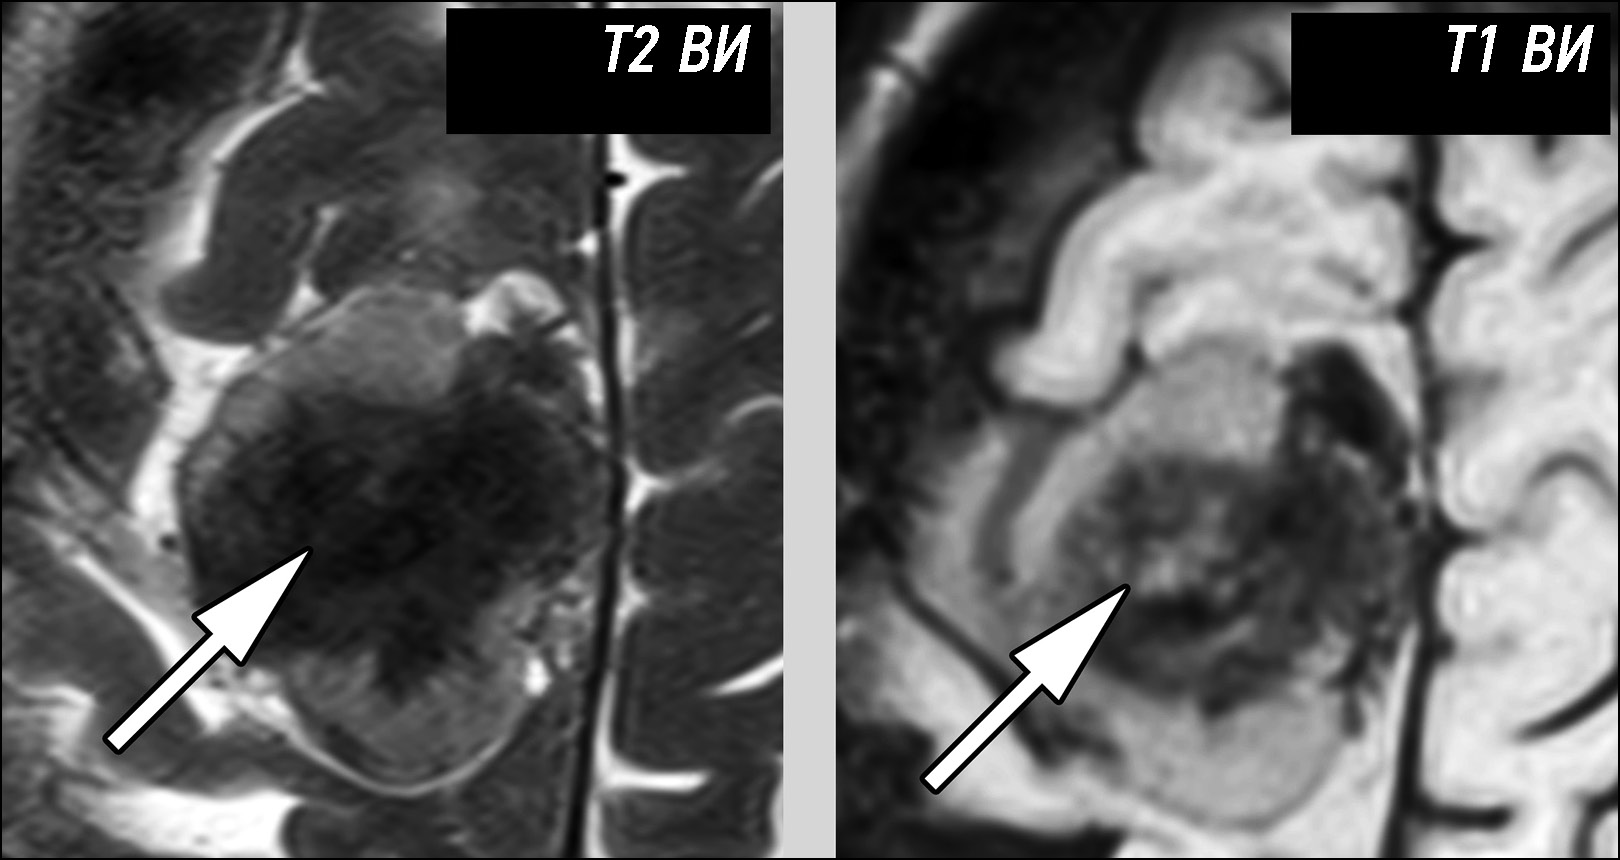

Инструментальная диагностика. При выполнении МРТ-исследования с внутривенным контрастированием (рис. 1) в передних отделах правой височной области выявлено внемозговое образование, размерами 1,9×1,4×2,0 см. Структура опухоли неоднородная за счёт участка с нечёткими контурами, имеющего гиперинтенсивный МР-сигнал на Т2-ВИ. На Т1-ВИ после внутривенного контрастирования (Т1-СЕ) отмечается выраженное, однородное повышение интенсивности МР-сигнала от выявленного образования с отсутствием контрастирования гиперинтенсивного на Т2-ВИ участка в его структуре. Выявленная зона была интерпретирована как участок некроза.

Рис. 1. Неоднородность структуры и гетерогенность контрастирования доброкачественной менингиомы. На магнитно-резонансной томографии признаки кисты (стрелка) схожи с проявлениями некроза.

Дифференциальная диагностика. Дифференциальный диагноз в данном случае следует проводить между доброкачественной и злокачественной менингиомами. Некроз характерен для злокачественных (Grade 2, 3) менингиом. В то же время у выявленного образования определяются признаки, типичные для доброкачественных менингиом (чёткое отграничение опухоли от вещества мозга, ровные контуры образования).

Наличие неоднородности структуры привело к ошибочному заключению о злокачественности выявленной менингиомы.

Инструментальная диагностика. По данным МРТ (рис. 2), в правой лобно-теменной области определяется внемозговое образование размерами 4,2×3,7×3,0 см. Структура опухоли неоднородная за счёт наличия зоны неоднородного гипоинтенсивного на Т2-ВИ МР-сигнала. Гипоинтенсивный на Т2-ВИ МР-сигнал может соответствовать как петрификации (типичной для менингиом Grade 1), так и отложению гемосидерина. Учитывая, что на Т1-ВИ в центральной части этой зоны определяется участок изо-/гиперинтенсивности, зона была интерпретирована как кровоизлияние, при петрификации МР-сигнал на Т1-ВИ был бы гипоинтенсивным.

Рис. 2. Неоднородность структуры доброкачественной менингиомы. Зона кровоизлияния (стрелка) придаёт структуре опухоли выраженную гетерогенность.

Дифференциальная диагностика. Кровоизлияние не характерно для доброкачественных (Grade 1) менингиом, но типично для солитарных фиброзных опухолей и злокачественных менингиом. Выявленное образование чётко отграничено от вещества мозга, признаков отёка по периферии нет, что типично для доброкачественных менингиом.

На основе этих фактов внемозговая опухоль была ошибочно классифицирована как атипичная менингиома.